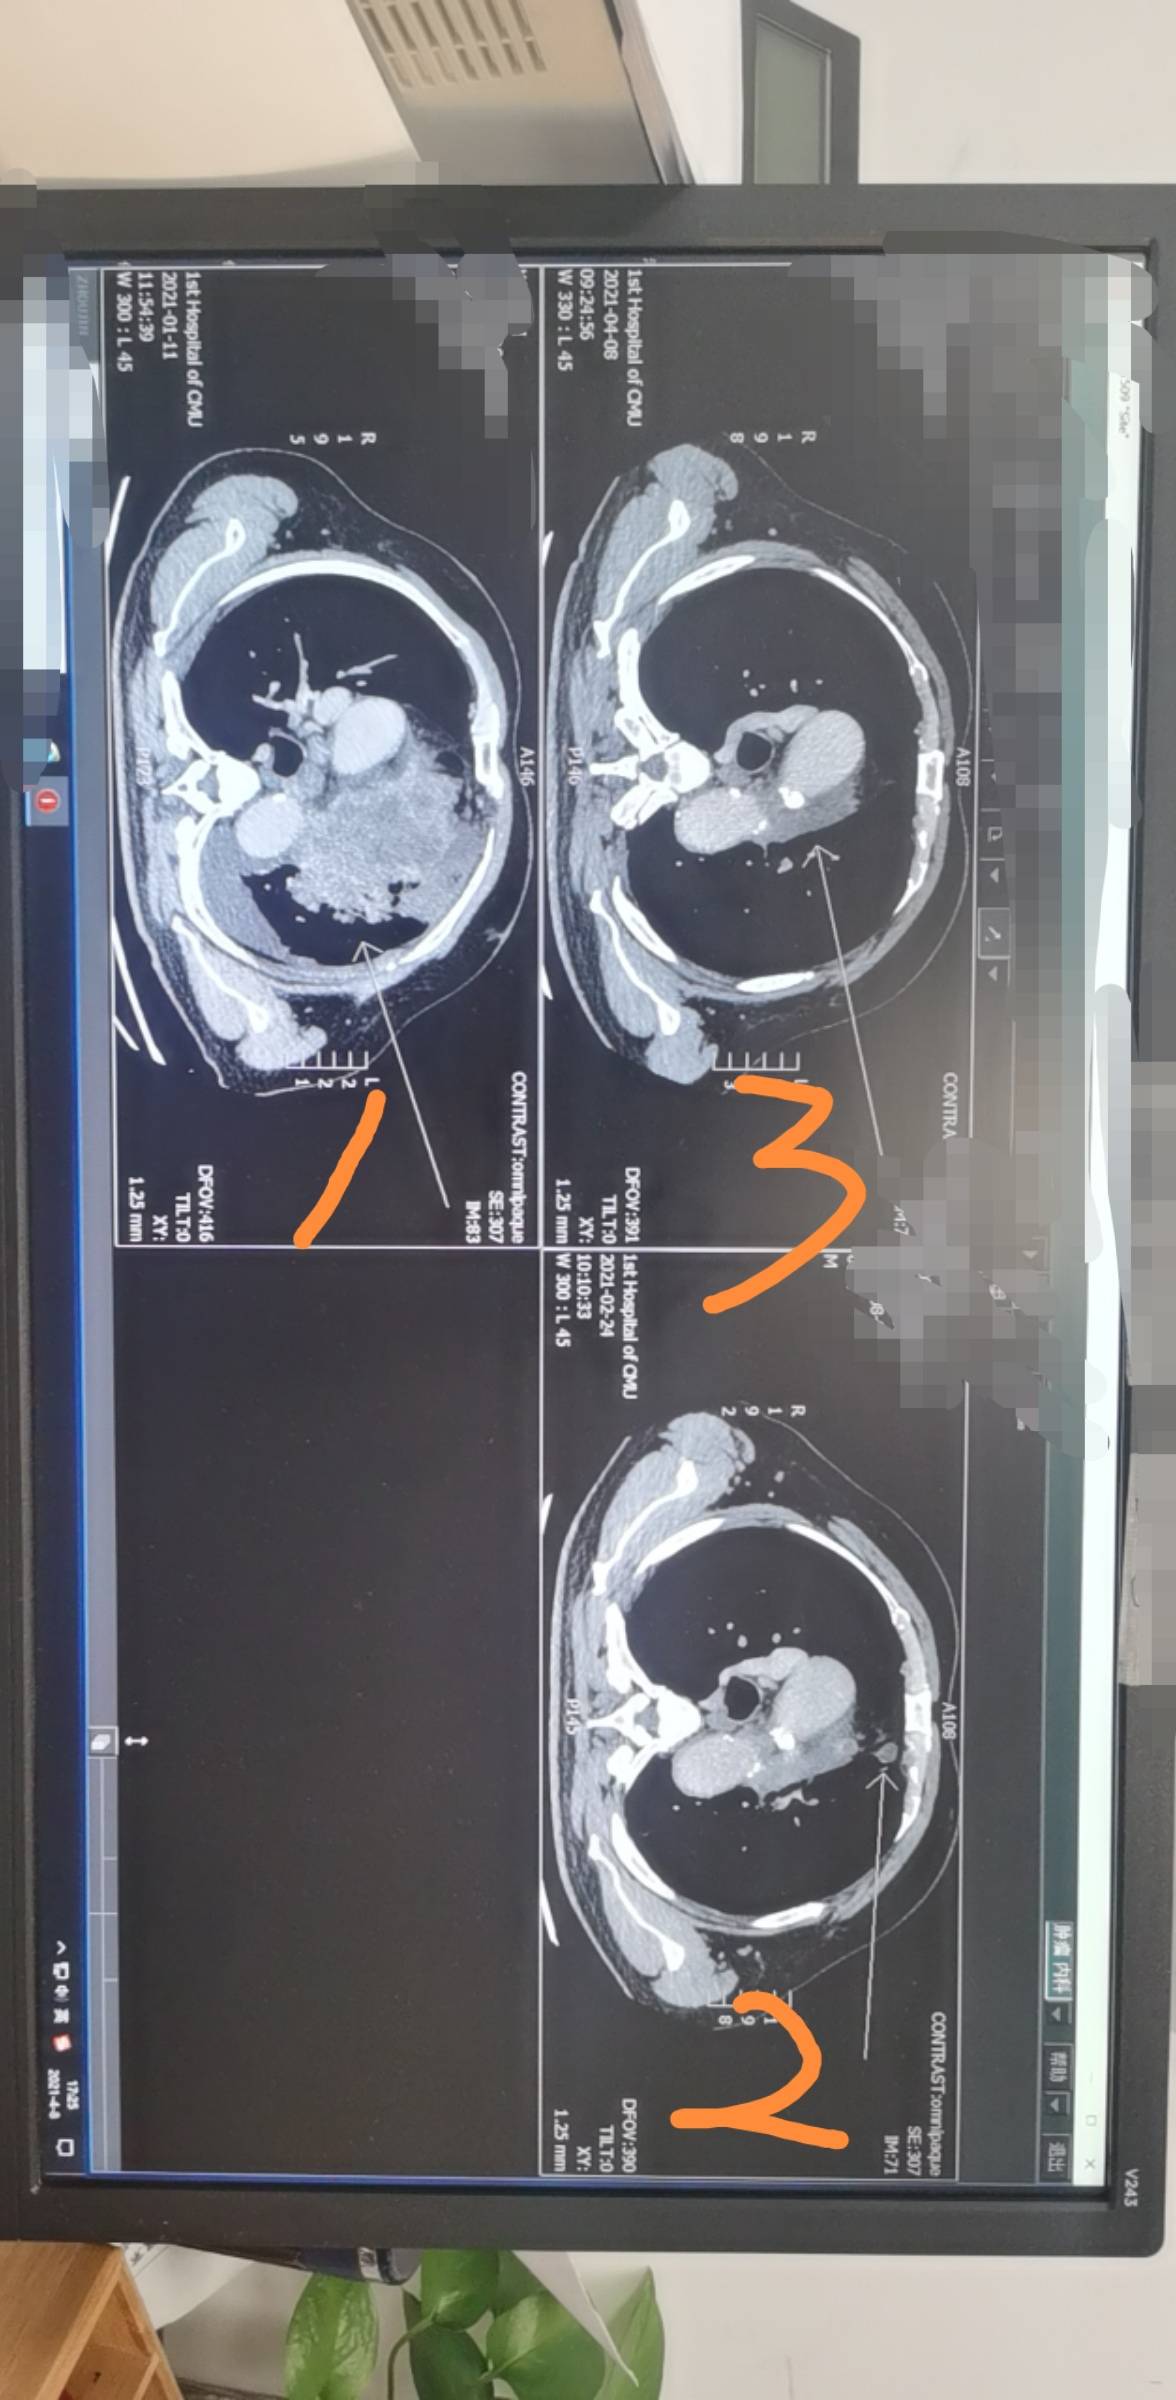

下面的几个图片是二化后的结果和四化后的检查结果,请各位病友大神帮忙看看,我们没耐药吧?坐等明天的癌胚抗原结果,祈祷祈祷🙏🏻🙏🏻🙏🏻

三次胶片对比: